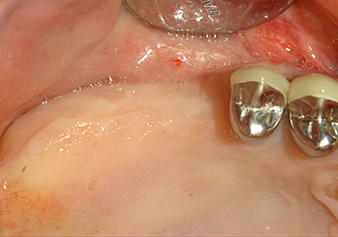

The I2A instrument (diameter 2.0 mm) was then used to perforate the sinus floor intermittently and on the smallest scale possible. This special piezosurgical method ensures that the Schneiderian membrane is not damaged. When the Z25P was used, the membrane was already lifted slightly by the coolant supplied via the instrument tip (Fig. 3). The coolant quantity was just 50% in order to avoid high pressure in the implant bed.